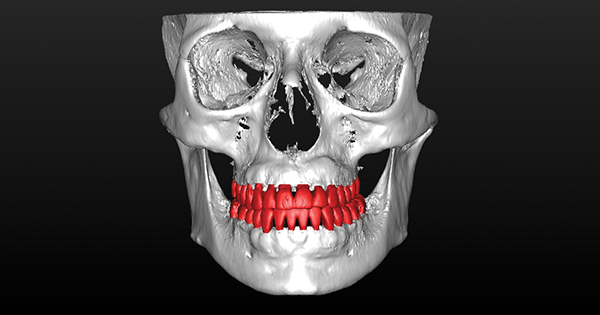

Fig 7. Preoperative CBCT 3D tooth position and regional bone anatomy. Note maxillary hypoplasia, malocclusion, and dentoalveolar deficiencies.

Figure 7

Fig 8. Preoperative CBCT 3D bone anatomy matched with postoperative CBCT final orthodontic tooth position. Note dental malocclusion correction

with significant detriment to the dentoalveolar bone. Orthodontic therapy would have exceeded the orthodontic walls and limits, causing

iatrogenic consequence.

Figure 8

Fig 9. Actual post-SFOT CBCT 3D tooth position with post-SFOT regional anatomy demonstrating alveolar augmentation

of the maxilla and mandible in conjunction with dental malocclusion correction. Dental malocclusion, dentoalveolar deficiencies, and

alveoloskeletal discrepancies have been addressed for comprehensive interdisciplinary management.

Figure 9